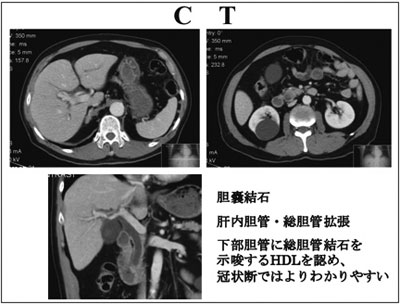

【CT】

造影CT では、胆嚢結石を認め、肝内胆管、総胆管拡張と下部胆管に総胆管結石を思わす High Density Lesion を認め、冠状断ではより わかりやすくなっている。

図7